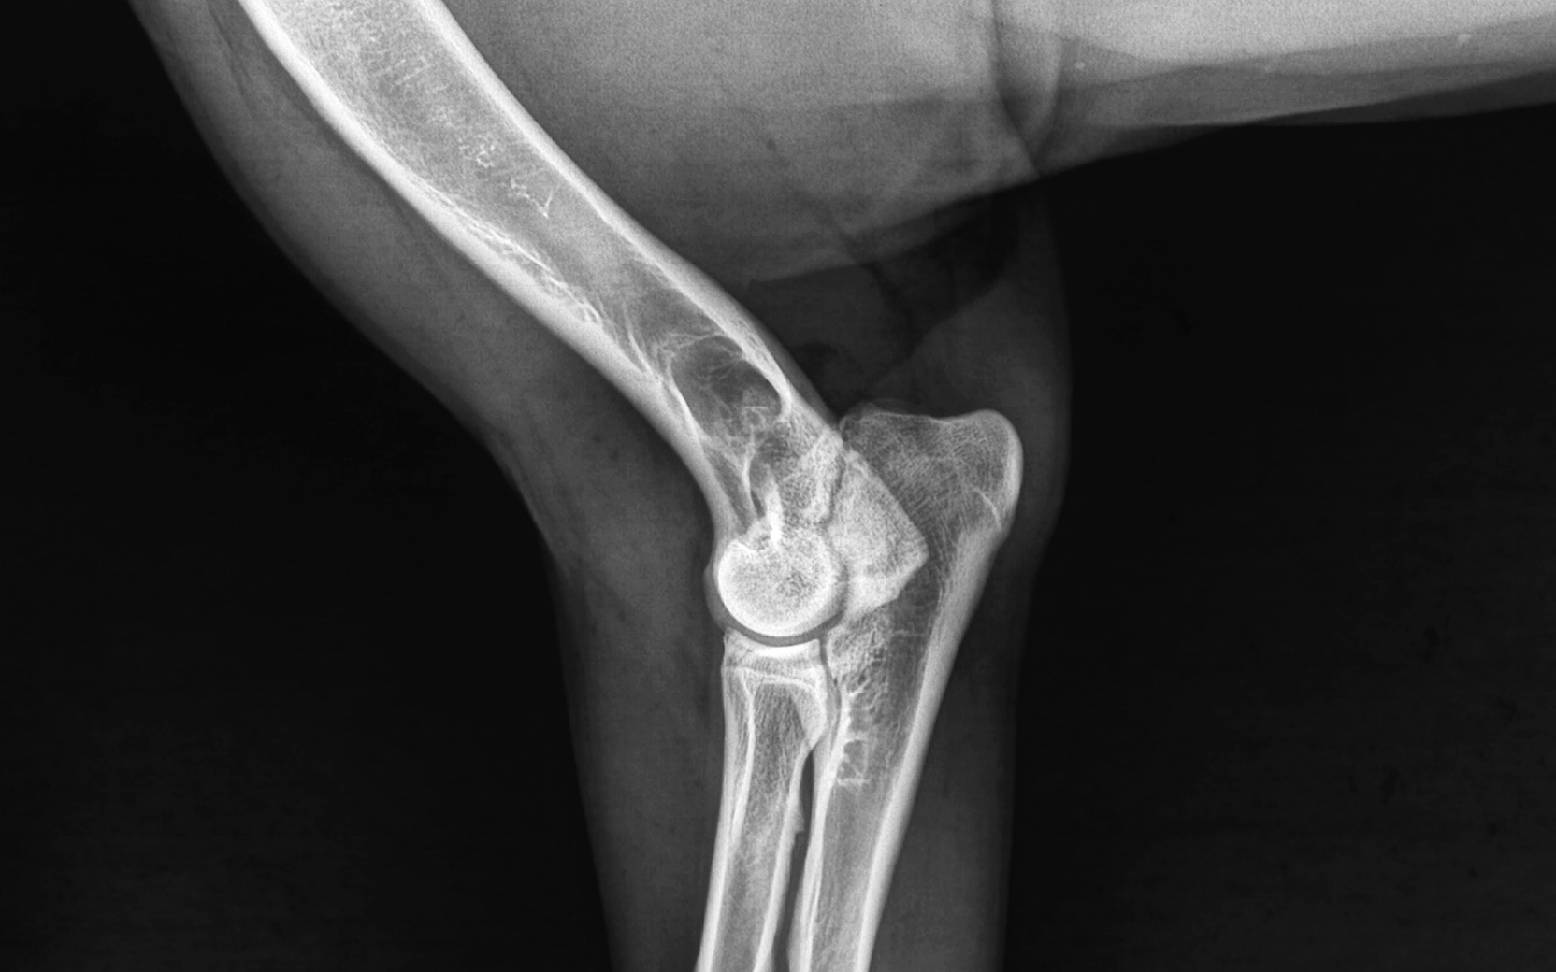

Anhand deines Vorberichts und der klinischen Untersuchung erhält dein/e Tierärzt:in schon wertvolle Informationen über eine eventuelle Erkrankung des Ellenbogengelenks. Zur Bestätigung der Diagnose und Differenzierung der Gelenkveränderungen werden Röntgenaufnahmen angefertigt. Zur besseren Vergleichbarkeit werden grundsätzlich beide Seiten geröntgt. Ist auch im Röntgenbild kein sicherer Nachweis möglich, kann nur eine Arthroskopie (=Gelenkspiegelung, siehe entsprechender Artikel) oder ein CT (=Computertomografie, siehe entsprechender Artikel) eine genaue Diagnose ermöglichen.

Durch die von vielen Zuchtverbänden vorgeschriebenen Röntgenuntersuchungen werden zahlreiche Fälle von ED diagnostiziert, bevor eine Lahmheit vorliegt.

Beim Hund reißt wie bei uns Menschen sehr häufig das vordere Kreuzband. Dieses feste Band verbindet im Kniegelenk den Oberschenkelknochen mit dem Schienbein und verhindert ein Überstrecken oder Verdrehen des Knies. Während der Kreuzbandriss beim Menschen jedoch meist traumatisch durch Sportunfälle jeglicher Art entsteht, kommt es beim Hund über einen längeren Zeitraum zu einer schrittweisen Degeneration (=Verschleiß) des Bandes.